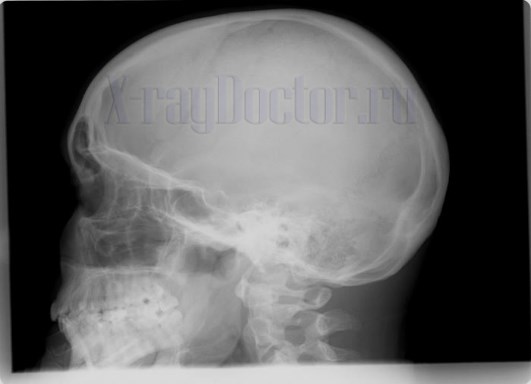

Рентген при определении степени перелома носовых костей выполняется сразу после прямого удара в область лица. Для рентгенодиагностики применяется прямая и боковая проекция, которые позволяют изучить состояние тканей.

Прямая рентгенография показывает только деструкцию со смещением. Для установления стороны повреждения делают снимки носа в левой и правой боковой проекциях. При этом больной вначале укладывается на левую сторону, а затем на правую сторону.

Симптом «воздушного пузыря» на рентгенограмме черепа и придаточных пазух носа в прямой проекции наблюдается на рентгеновском снимке при попадании воздуха в лобную часть черепа. Воздушный пузырь на снимке локализуется в области свода и лобных костей.

Таким образом, рентген сломанного носа является необходимым исследованием, позволяющим обнаружить переломы на ранних сроках. Исследование используется также для динамического наблюдения за срастанием носовых костей. Оно является необходимым на этапе предварительной оценки повреждений после травмы лица. В травматологии без рентгенографии невозможно подбирать оптимальные тактики лечения.